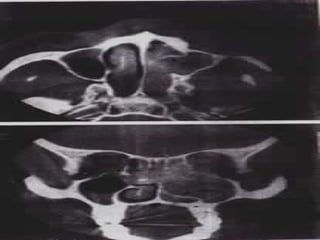

◦ TAC: permite ver la extensión y erosión. La presencia de

calcificaciones dentro del tumor muestra el hueso

atrapado, la erosión del mismo se observa más como

una atrofia, que como una invasión.

◦ RM: permite evaluar compromiso de cavidad craneana y

órbita.